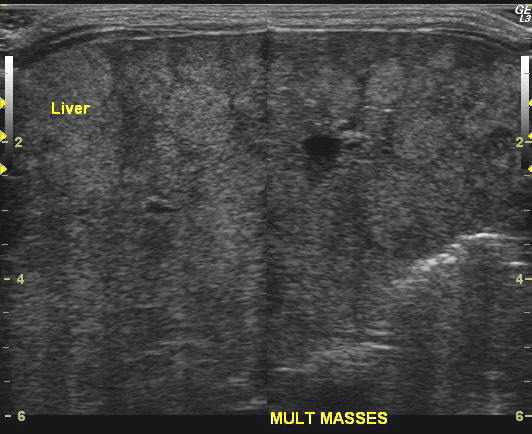

The above ultrasound and color Doppler images show multiple echogenic, poorly vascular masses throughout the liver in this neonate. The left kidney shows a poorly defined mass in the upper pole. The right kidney appears normal. A provisional diagnosis of neuroblastoma was made on these sonographic findings. However, it was felt that CT scan would be of better diagnostic importance. CT scan images of this neonate are shown below (coronal and sagittal reformatted images). The CAT scan images of this neonate confirmed the presence of a left suprarenal mass, which was hypodense and poorly enhancing. The left kidney was also found to be displaced laterally and downwards. These findings confirmed a left adrenal neuroblastoma with metastases to the liver. The liver shows massive hepatomegaly.